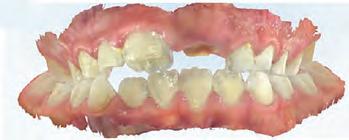

A 31-year-old woman presented with cosmetic concerns regarding her smile and requested a conservative enhancement. After clinical and radiographic analysis, digital 35mm photographs were taken and reviewed by the restorative clinician, technician, and surgeon (Fig 1). A digital impression was taken of the maxillary and mandibular arches using an intraoral scanner (Trios 3, 3Shape; Fig 2), and a smile design was developed with NemoSmile Design 3D software (Nemotec; Fig 3a). This allows for a facially driven smile frame to be created using reference lines of facial and smile proportions and natural teeth shapes and textures from the digital library (Fig 3b).

After developing the simulated mock-up, a 3D-printed resin model was created using CAD software (Fig 4a), and a clear PVS matrix (Exaclear, GC America) was fabricated to replicate the printed diagnostic wax-up using a nonperforated tray (Fig

Fig 1 Preoperative clinical views of a 31-year-old woman presenting with diastemas and limited tooth visibility. (top) Portrait. (center row) Intraoral views. (bottom row) Smile.

4b). This matrix was used to create an intraoral motivational mock-up with bis-acryl composite (Luxatemp Ultra, DMG). This additive mock-up provides the interdisciplinary team with an intraoral translation for evaluation (Fig 5). Upon evaluation of the digital smile frame and the clinical translation, it was determined that multiple esthetic and restorative requirements were necessary for an optimal biologic framework, and the interdisciplinary team determined the best sequence for these procedures. The patient was presented with the interdisciplinary treatment possibilities that included restoring the maxillary anterior teeth and premolars with a minimally

invasive preparationless procedure or with less conservative veneer preparations. The restorative materials discussed included injectable resin composites and ceramic (ie, feldspathic, pressable, machinable). For an optimal biologic framework and health, it was determined that connective tissue grafting would be necessary for treatment of the recessiontype defects on the maxillary left central and lateral incisors, canine, and premolars. The patient opted for the conservative preparationless composite veneers using the injectable resin technique followed by a connective tissue surgical procedure using the tunneling technique.